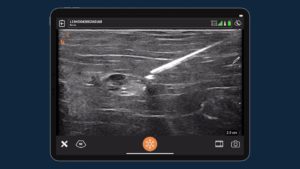

Dr. Rosenblum is one of the few doctors that is trained and skilled to use ultrasound,” says Regina. “Most of the other doctors, when they give you the injection, they’re really going blind…. They’re looking at your MRI and then trying to blindly go and find that exact location. When Dr. Rosenblum is giving you the injection, he is basically using live ultrasound and visualizing the nerve and then getting that exact location that he wants.”

Dr. Rosenblum uses the Clarius L7 HD high frequency handheld ultrasound scanner for his practice, which he says works well for all of his ultrasound-guided pain management procedures, shallow and deep. He has been a Clarius user since 2017.